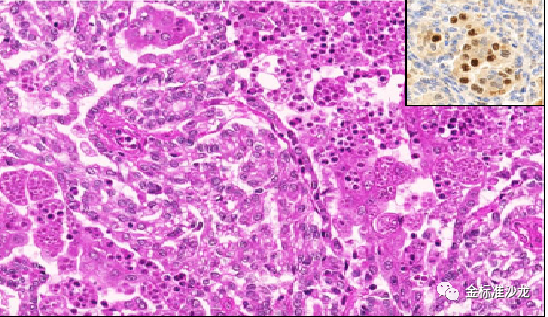

因常存在乳头状或管状乳头状癌区域和高级核特征,包括过去常被错误诊断为2型pRCC的还包括MiTF家族(包括TFE3重排的和TFEB重排的RCC和TFEB扩增RCC,图2,3),新的实体嗜酸性实体和囊性(ESC)-肾细胞癌,管状囊性肾细胞癌和集合管癌。另一个实体粘液管状和梭形细胞癌由于具有不同的染色体改变和Hippo通路肿瘤抑制基因的双等位基因失调,已独立于1型pRCC,尽管二者存在形态及免疫组化重叠。

fh染色是什么意思WHO2022年分类:乳头状肾细胞癌进展介绍_https://www.jmylbn.com_新闻资讯_第3张

图3 TFEB扩增的RCC具有类似特征,通过FISH进行TFEB检测能够确定诊断